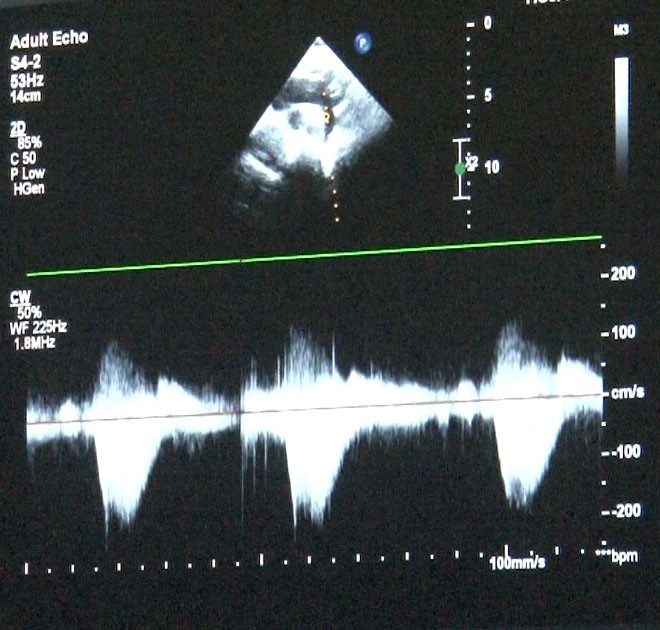

‘Sağlık Bakanlığı verilerine göre her yıl bin canlı doğumdan 8’inde doğumsal kalp hastalığı görebilmekteyiz’ diyerek sözlerine başlayan Uzm. Dr. Damla Gökçeer Akbulut, “Yılda 12 bin çocuk doğumsal kalp hastalığıyla dünyaya geliyor. Çeşitli nedenleri olabiliyor bazen annenin gebelikte kullandığı ilaçlar ya da diyabet gibi bir hastalığı olması, genetik rahatsızlıklar, bunlar genetik olarak kalp rahatsızlıklarına yol açabiliyor. Bu hastalarda erken tanı mümkün, daha anne karnındayken fetal ekokardiyografi (anne karnındaki bebeğin kalp yapısını ve işlevini değerlendirmek amacıyla kullanılan bir tıbbi görüntüleme)yle doğumsal kalp hastalığı olan bebeklerde doğum sonrası erken müdahale yapabiliyoruz. Bazı bebekler mor doğabiliyor ancak bazılarında bu bulgular ilk ay içinde gelişebiliyor” dedi.

Uzm. Dr. Gökçeer Akbulut ise, “Ailede daha önceden tanısı olmayan doğumsal kalp hastalığı olan bir bebek olduğunda hızlı nefes alıp verme, morarma ya da emerken soğuk terleme gibi bulgular varsa mutlaka çocuk hekimi kontrolünde bir çocuk kardiyoloğuna hızlıca yönlendirilmesi lazım. Doğar doğmaz müdahale edilmediğinde yaşamsal olabilecek sorunlarla karşılaşabiliyoruz, hasta kaybedilebiliyor. Anne karnında olmuyorsa da doğar doğmaz ekokardiyografi yaparak tanısını koymak mümkün. Hastalarda viral enfeksiyon ve kış döneminde RSV virüsü, ilk 2 yaştaki çocuklarda sık gördüğümüz bir viral enfeksiyon, sezonuna girmiş bulunmaktayız. Doğumsal kalp hastalığı olan çocuklarda ekim, mart ayları arasında mutlaka RSV aşılaması yapılmasını tavsiye ediyorum. İnfluenza dediğimiz belirtiler varsa ya da covid sonrası miyokardit dediğimiz kalp kası iltihabı görebiliyoruz. Çok ciddi boyutlarda şok tablosu dediğimiz tansiyon düşüklüğü, taşikardi dediğimiz nabız hızlanması ve solunum yetersizliği bulguları, hastada ödem artışı, hızlı nefes alıp verme gibi bulgularla yoğun bakım yatışı gerektirebiliyor. Kalp hastası olduğundan emin olduğumuz bir çocukta yıllık aşılamalarına influenza açısından devam edilmesini öneriyoruz” diye konuştu.